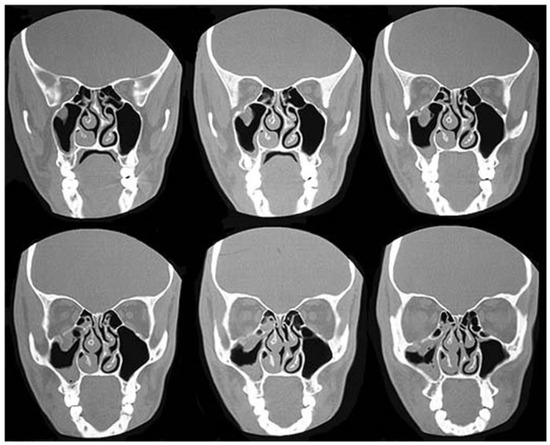

Figure 3. Cranium-to-face ratio. At birth and in early childhood, the cranium represents a relatively large volume of the craniofacial complex (8:1 and 4:1, respectively). Cranial and orbital fractures are therefore more common during this time. The cranium-to-face ratio in the adult is ~2:1.

Although the frontal bone is membranous at birth, there is seldom more than a recess present until the bone begins to ossify around age 2. Thus, radiographs rarely show this structure before that time. Frontal sinus pneumatization begins at ~7 years of age and completes development during adulthood. In children, frontal bone and orbital roof fractures are commonplace because of the high cranium-to-face ratio (Figure 3) and incomplete (or absent) pneumatization of the frontal sinus. In addition, the supraorbital rim and frontal bone are the most prominent structures on the pediatric craniofacial skeleton; consequently, they sustain the brunt of initial impact. In the adult skeleton, however, the frontal sinus, supraorbital rim, and frontal bone protect the brain and orbital cavity from injury [3]. Koltai et al reviewed a series of orbital fractures in children aged 1 to 16 years. Based on their data, they determined that at age 7, orbital floor fractures become more common than orbital roof fractures [4]. The orbital floor becomes more susceptible to fracture in later childhood. Similar results were described by Fortunato and Manstein [5]. This age coincides with development of the maxillary sinus, as stated previously. Incidentally, the orbit reaches an adult size at approximately the same age.

Epidemiology

In developed countries, trauma is the leading cause of death among children. A review of the National Trauma Databank, 2001 to 2005, identified 12,739 facial fractures among 277,008 pediatric trauma patient admissions (4.6%) [7]. The relative paucity of facial fractures in children—when compared with adults—has been previously demonstrated [8,9]. The preponderance of elastic, cancellous bone and the aforementioned high cranium-to-face ratio in children (Figure 3) are responsible for this finding. As a corollary, children are more likely to sustain skull fractures and brain injuries than facial fractures [10,11,12]. Indeed, facial fractures are rare before the age of 5 [13]. Rowe, for example, reported that only 1% of all facial fractures occur in children 1 year old or younger [14]. These results were echoed by other series [1,9,15], although the incidence may be underestimated, as these studies predate the use of routine computed tomography (CT) scans in craniofacial trauma [16].